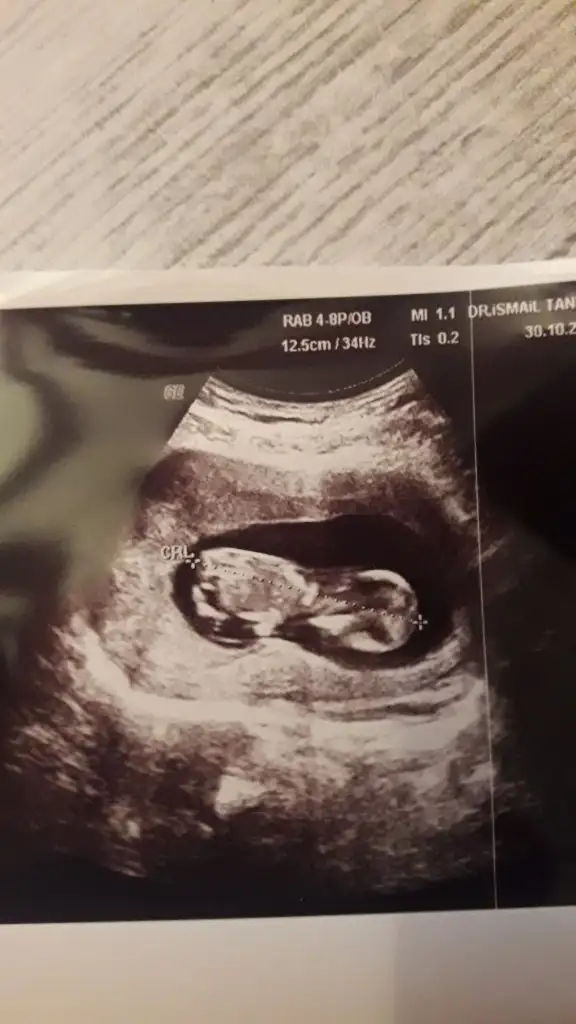

Merhaba bizim bebiş ters duruyor secde pozisyonunda ultrasona göre 12+3 benim bebişim içinde bir tahminde bulanabilirmisiniz rica etsem.

Eklentiler

• 20191030_174024.webp

20191030_174024.webp

24,7 KB · Görüntüleme: 63